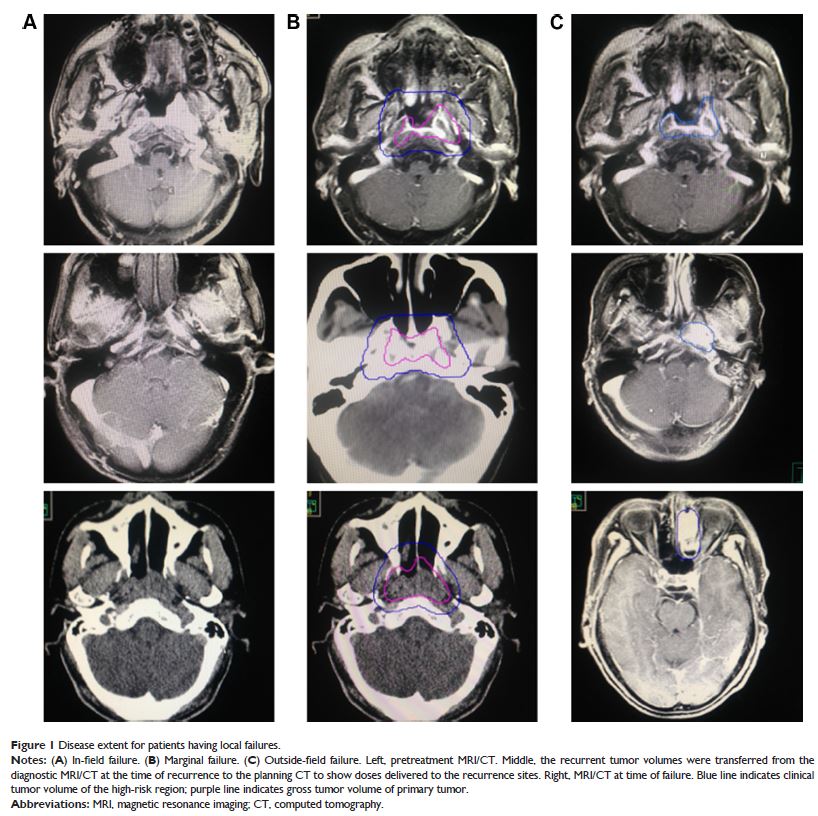

Original Research

- 作者:Yujiao Li, Xiaomin Ou, Chunying Shen, Tingting Xu, Weiwei Li, Chaosu Hu

- 期刊:OncoTargets and Therapy